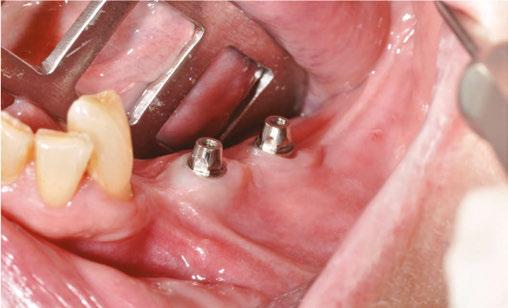

The procedure begins with local anesthesia at multiple points, vestibular and lingual, from the symphyseal region to the ascending ramus. However, an infiltration in the lingula of the mandible is not necessary. The incision is performed using the technique described above (Figures 5A and 5B).

It is imperative to carefully reflect a full-thickness flap following the periosteum. After reflection, an atraumatic periosteal expansion using a soft brush (Figure 6) will allow for the flaps to be repositioned without tension over the implant and bony surfaces at the end of the procedure.

Figures 8A-8D: Placing the subperiosteal implant and monitoring its adaptation Figures 5A and 5B: 5A. Initial clinical view. 5B. Access flap Figure 6: Periosteal expansion using a soft brush Figure 7: Prehension of the subperiosteal implant

After the soft tissue is prepared, the bony surface is carefully cleaned. For easy insertion, the healing abutments are left in place, and the implant is held firmly with hemostatic forceps (Figure 7). The implant is inserted via distal translation in the direction of the angle of the mandible, then a mesio-anterior rotation. The surgeon must control the lack of mobility and the adaptation of the implant to the bony surface at all points (Figures 8A, 8B, 8C, and 8D).

To ensure the implant is stable during the osseointegration period, an osteosynthesis screw is placed in the prepared space (Figures 9A, 9B, 9C, and 9D).